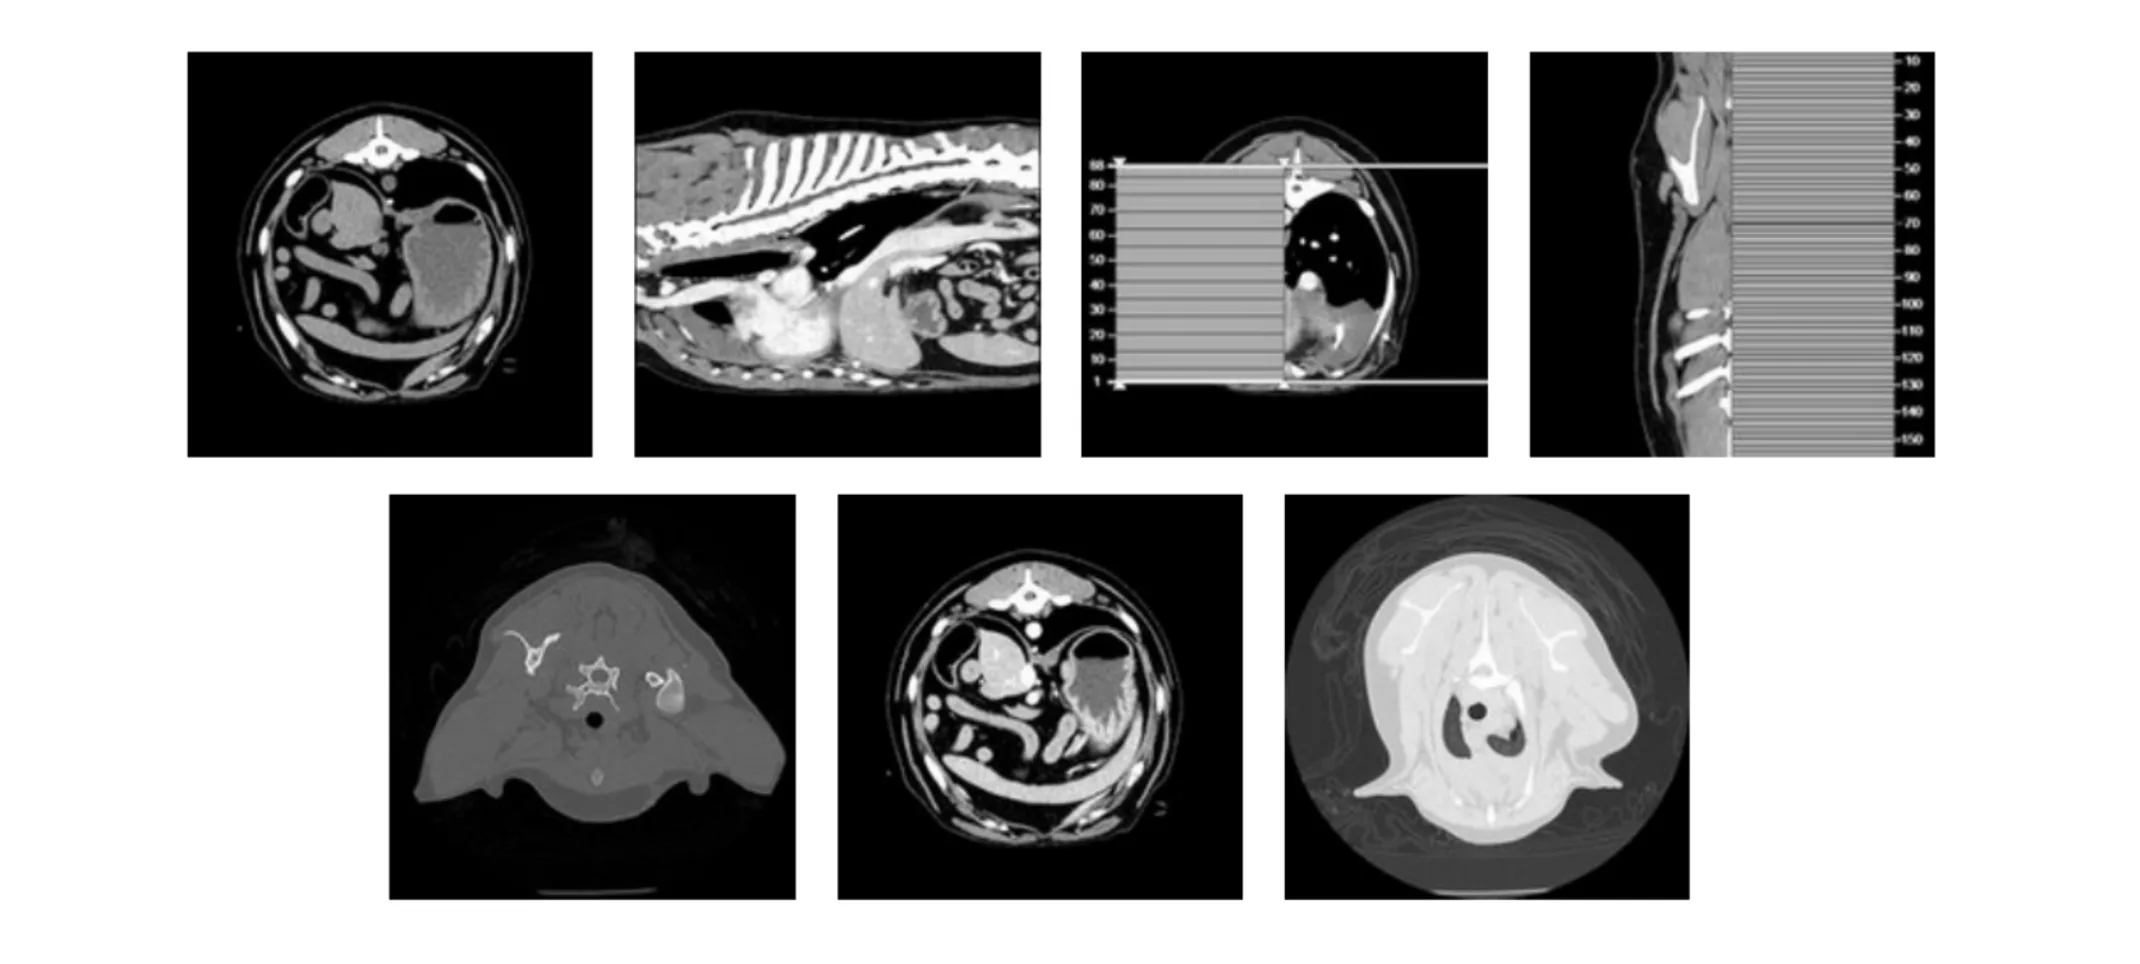

Thoracic CT Scan (05-29-2024):

Findings: While the CT scan focused our attention on the cranial mediastinum, the quills themselves were not apparent on the imaging. This ambiguity necessitated a comprehensive approach to ensure that no lung area, left or right, was overlooked.

Interpretation: The CT findings were critical in guiding the decision for surgical exploration, leading to the choice of a median sternotomy to access the entire chest space for thorough examination and treatment.